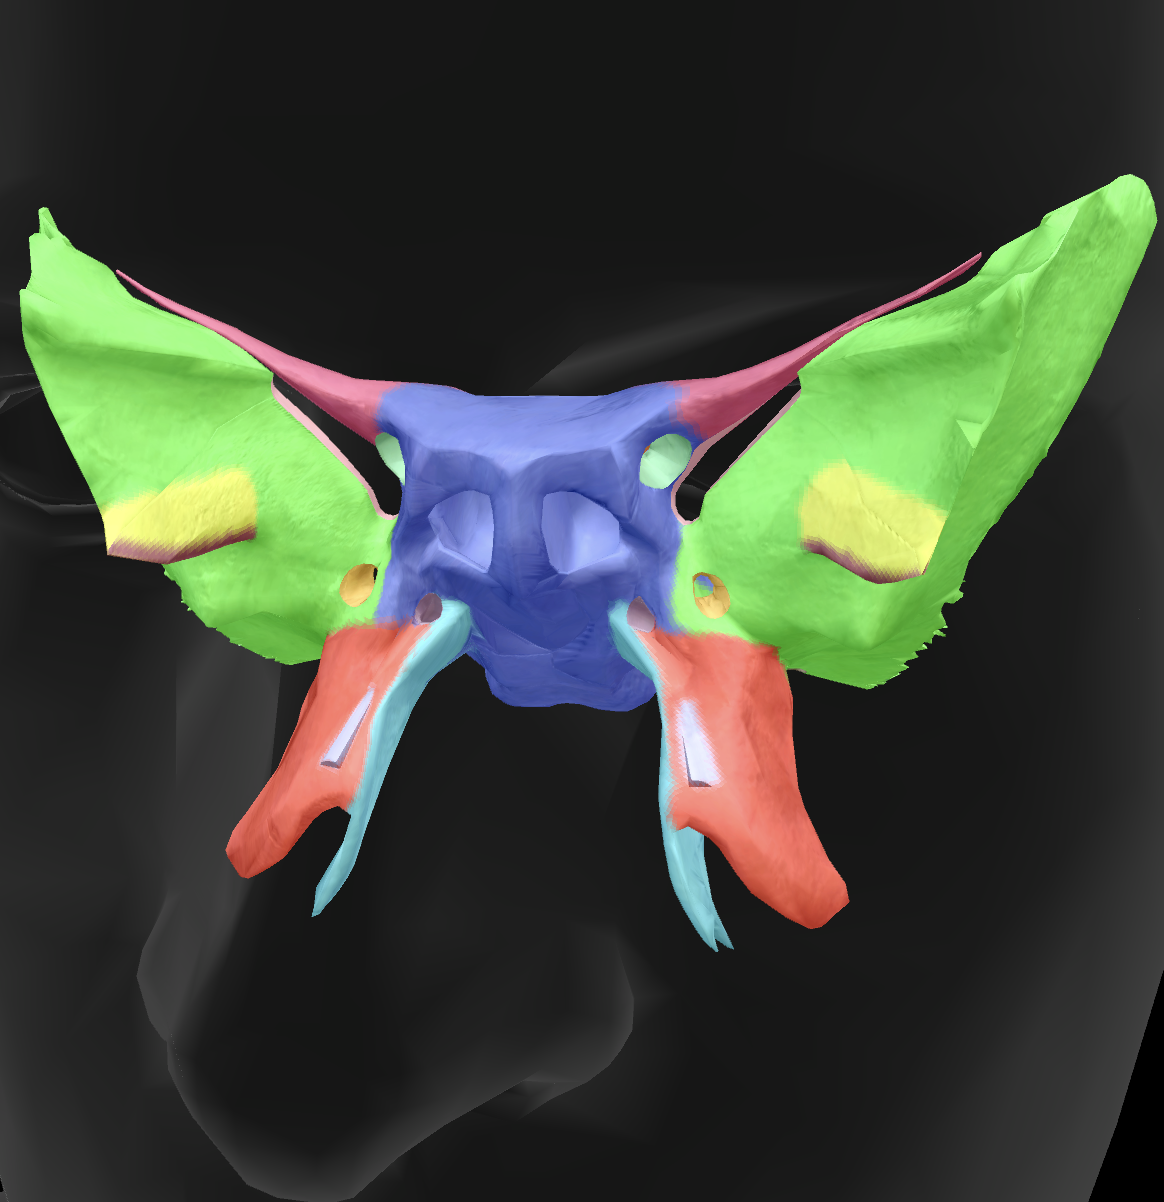

What is the name of this bone?

sphenoid bone

body

What is the name of this feature?

lesser wings

What is the name of this feature?

sella turcica

What is the name of this feature?

greater wings

What is the name of this feature? (the hole)

optic foramen

What is the name of this feature?

lateral pterygoid plate

What is the name of this feature?

medial pterygoid plate

What is the name of this feature?

superior orbital fissure

What is the name of these holes?

foramen rotundum

What is the name of these holes?

foramen ovale

What is the name of these holes?

foramen spinosum